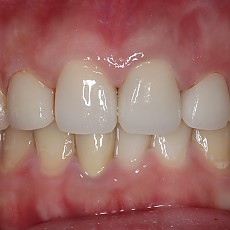

시술전후사진 6 페이지

Total 189건 6 페이지